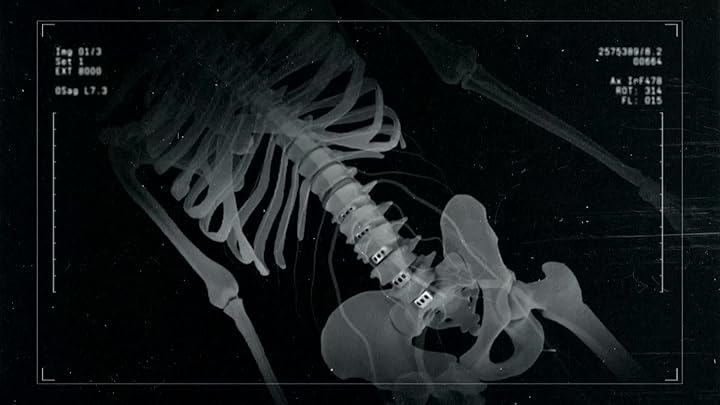

Surgeons at University Hospital Southampton perform intense and complex procedures to save patients' lives. In this episode the consultants carry out high risk spinal surgery and attempt to repair a section of the body's biggest blood vessel that's threatening to burst.